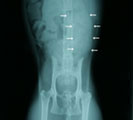

結腸内に巨大な宿便あり 手術所見。プレート設置 直後。骨盤が十分拡幅 術後1ヶ月。普通に歩く。

経過:受診時、レントゲンにて骨盤の恥骨前縁に骨の変形あり骨盤腔側に突出していた。そのため排便障害が生じ結腸内に巨大な宿便がみられた。恥骨前縁の変形は交通事故の影響によるものと考えられた。恥骨部分の突出部を削ったとしても再び術後増殖して再び骨盤腔が狭窄する可能性が高いので、矢田式骨盤拡幅プレート設置を行った。術直後の腹部レントゲンにて秘結便が十分通過できる程度、骨盤が拡幅されていることを確認した。術後経過は極めて良好で、毎日排便がみられるようになった。術後2-3日は軽度開脚して歩行していたが次第に正常歩様になり、1ヶ月後には歩行に何も問題がみられなくなった。